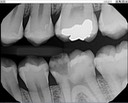

Scott Kanamori #12 pre-op

Scott Kanamori #12 caries removal

Scott Kanamori #12 prep